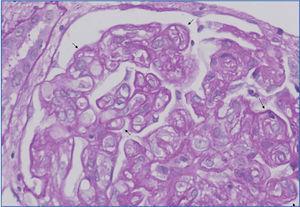

b. Neutrophils and/or mononuclear cells in peritubular capillaries and/or glomerulus, and/or capillary thrombosis (Figure 1),

Figure 1. Congestion and presence of inflammatory cells in peritubular capillaries